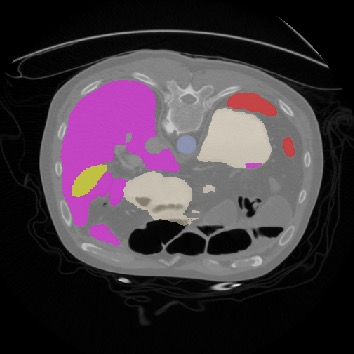

Transformers, the default model of choices in natural language processing, have drawn scant attention from the medical imaging community. Given the ability to exploit long-term dependencies, transformers are promising to help atypical convolutional neural networks (convnets) to overcome its inherent shortcomings of spatial inductive bias. However, most of recently proposed transformer-based segmentation approaches simply treated transformers as assisted modules to help encode global context into convolutional representations without investigating how to optimally combine self-attention (i.e., the core of transformers) with convolution. To address this issue, in this paper, we introduce nnFormer (i.e., Not-aNother transFormer), a powerful segmentation model with an interleaved architecture based on empirical combination of self-attention and convolution. In practice, nnFormer learns volumetric representations from 3D local volumes. Compared to the naive voxel-level self-attention implementation, such volume-based operations help to reduce the computational complexity by approximate 98% and 99.5% on Synapse and ACDC datasets, respectively. In comparison to prior-art network configurations, nnFormer achieves tremendous improvements over previous transformer-based methods on two commonly used datasets Synapse and ACDC. For instance, nnFormer outperforms Swin-UNet by over 7 percents on Synapse. Even when compared to nnUNet, currently the best performing fully-convolutional medical segmentation network, nnFormer still provides slightly better performance on Synapse and ACDC.